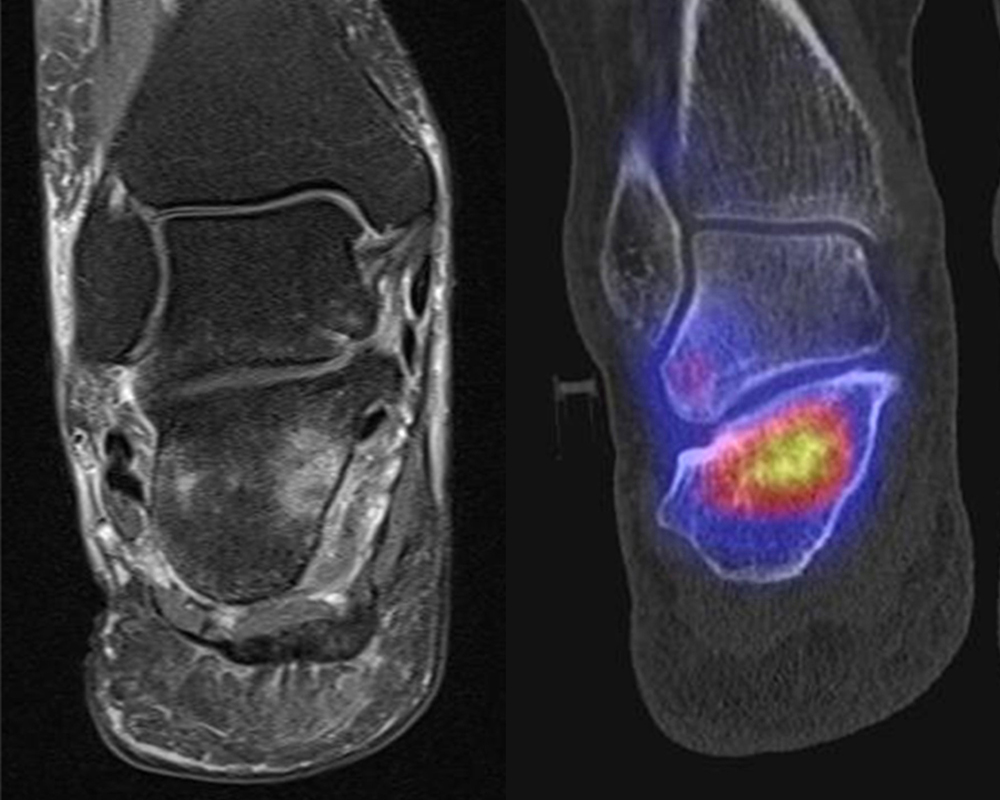

Abbildung 2.1.

Bildbeispiele symptomatische OCL

Zum Lesen der Bildbeschreibung und zur Vollansicht bitte das Bild anklicken. Bild: H. C. Rischke

Abbildung 2.2.

Bilder eines Patienten mit Z. n. mehrfachen Sprunggelenksdistorsionen in der Vergangenheit, besonders heftige Distorsion des linken Sprunggelenkes 5 Wochen vor der Untersuchung. Die SPECT/CT zeigt eine instabile osteochondrale Läsion mit deutlicher Aktivierung.